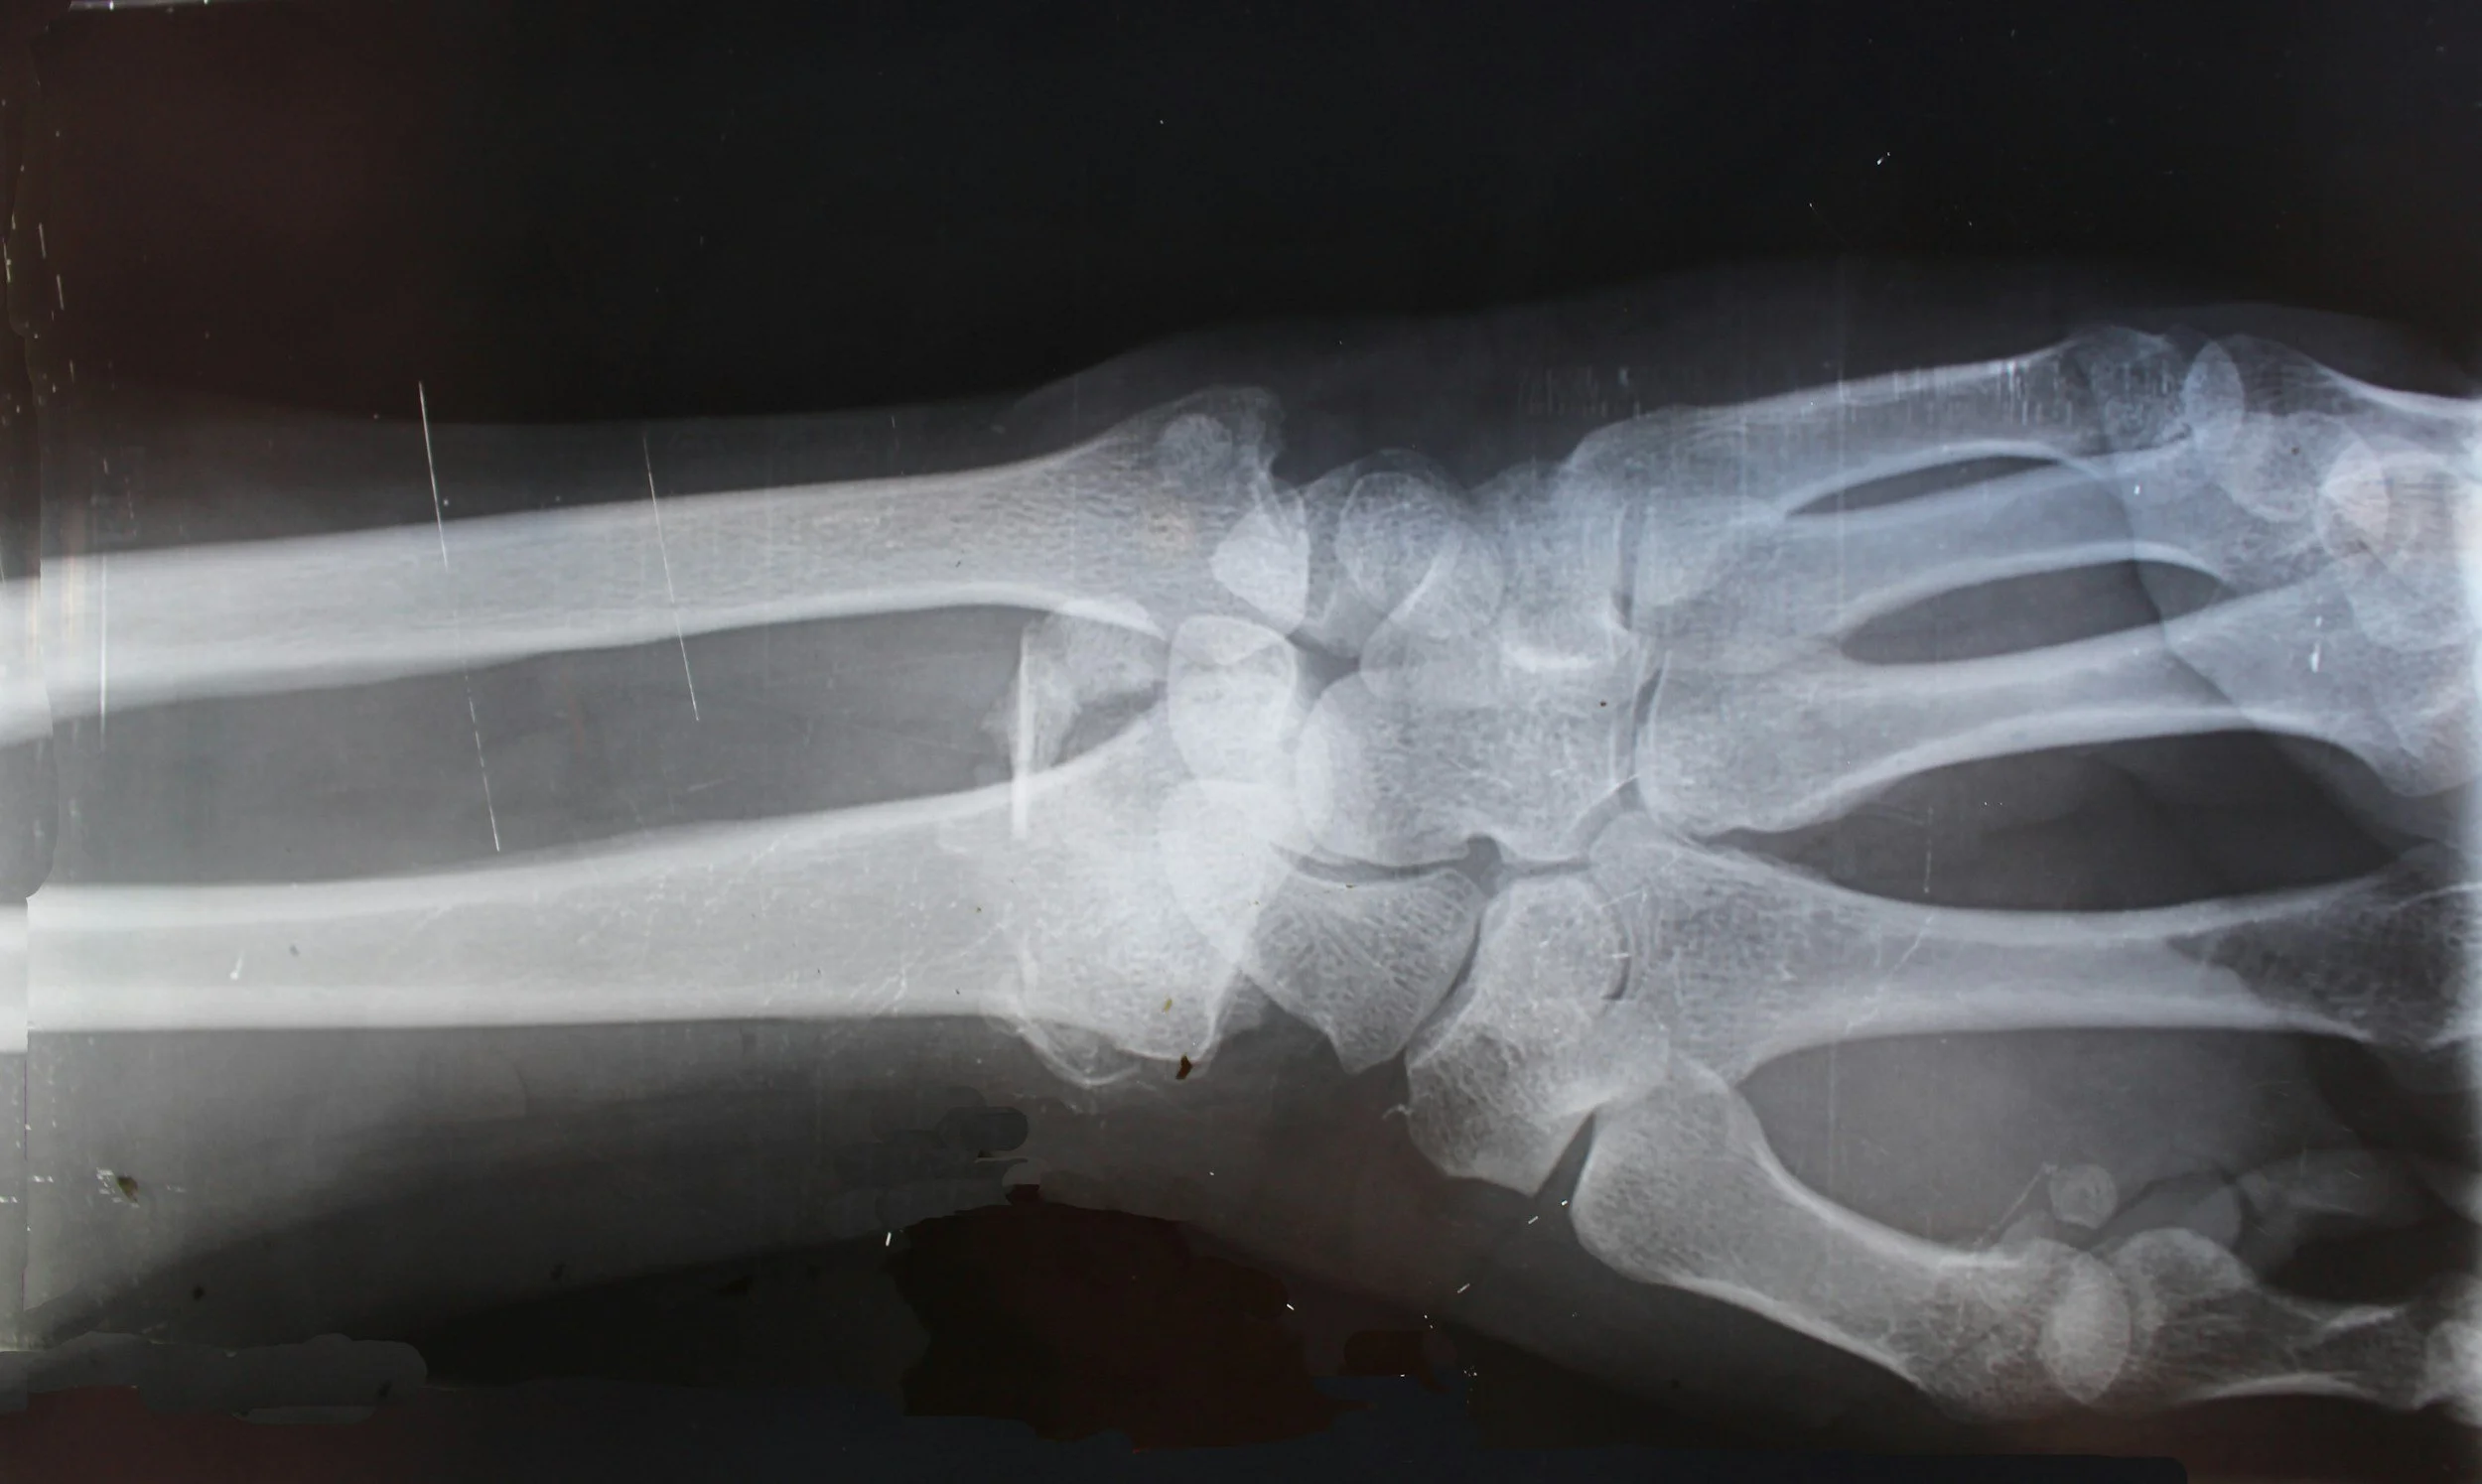

X-ray image of a human hand and wrist, showing bones including the fingers, knuckles, and wrist joints.

With X-rays on site, Fast Track Urgent Care can diagnose a wide array of illnesses and injuries and help identify the best treatment plan right away. They use our digital X-rays to scan several parts of the body, including foreign bodies in soft tissues, bones, joints, and more.

Whenever you have an accident, Fast Track Urgent Care is ready to help get you on the road to recovery. By using our digital X-rays, we can better determine the type of injury that you have as well as its severity. Then, our providers can recommend a plan of care and any next steps, which may include a referral to the emergency room or a specialist for the next step in care.